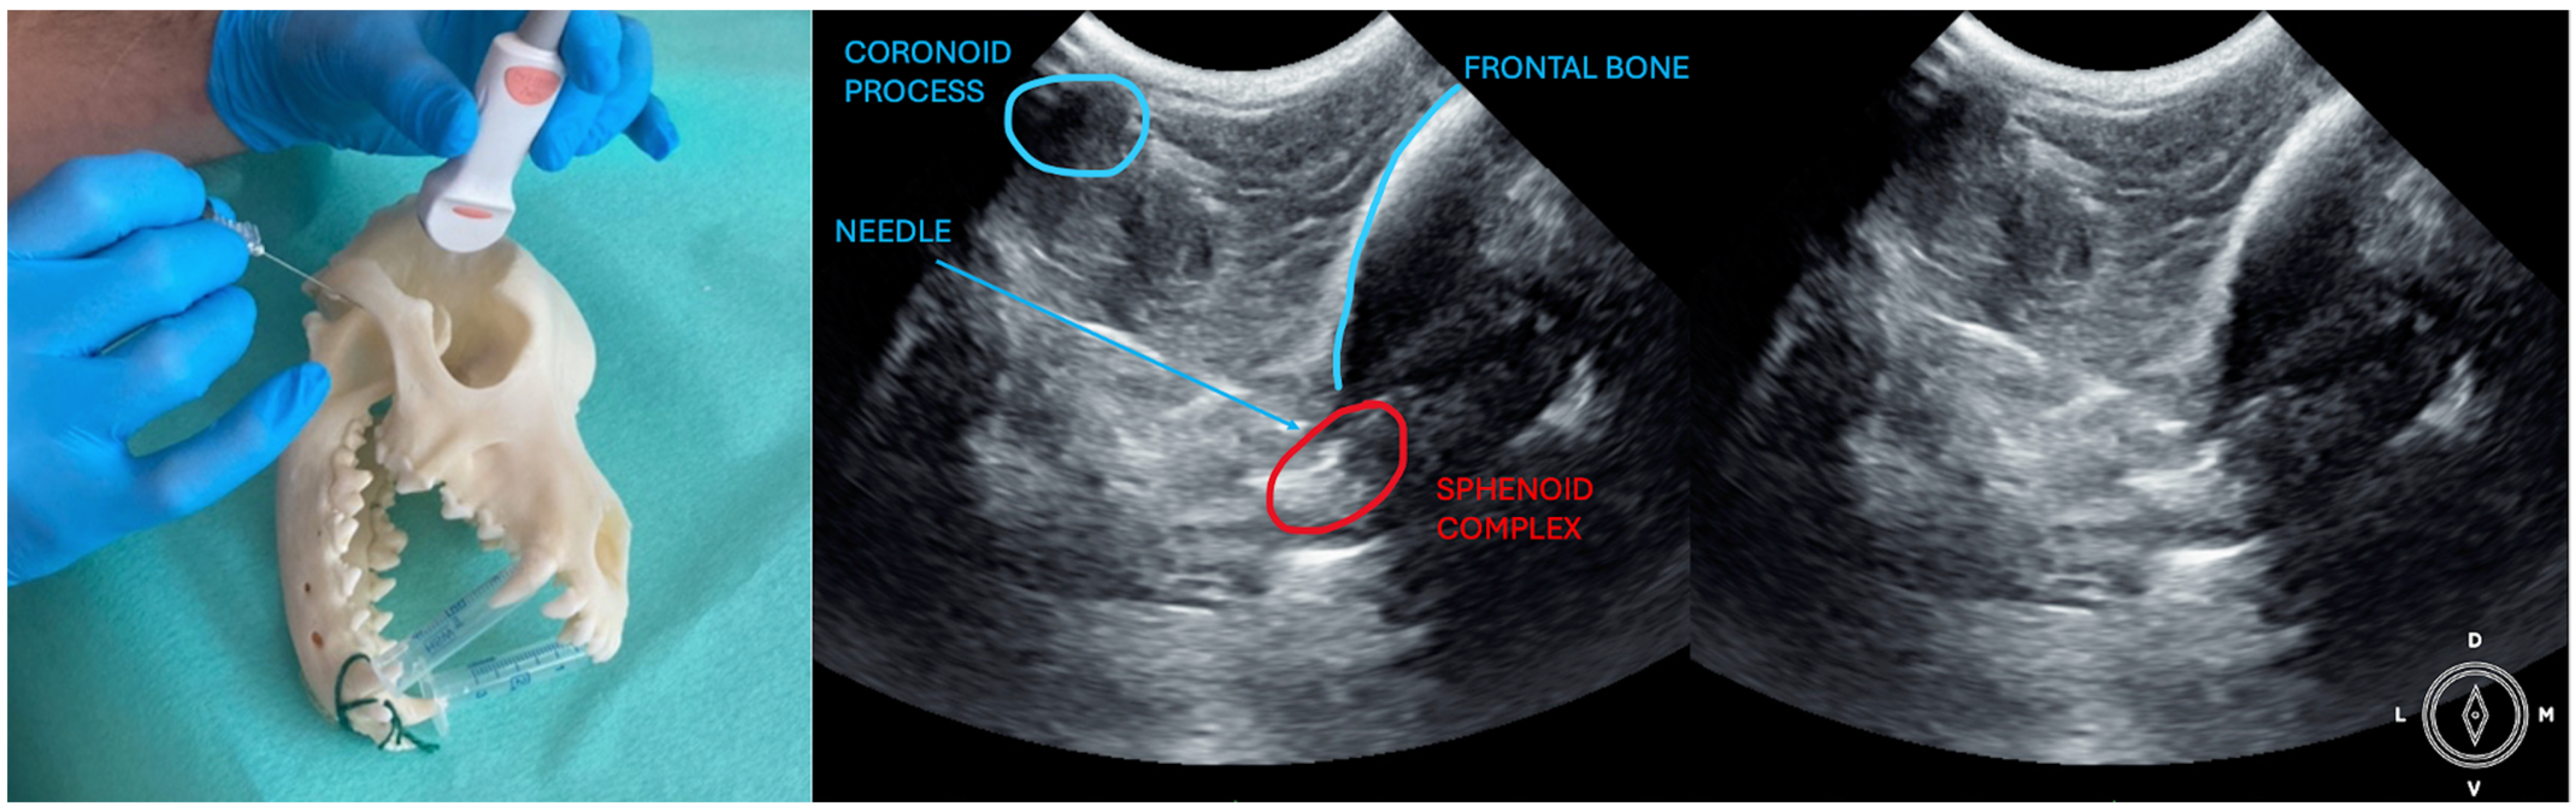

The ultrasound probe was positioned over the temporal region immediately caudal to the orbital ligament to obtain a transverse view of the caudal portion of the pterygopalatine fossa for both approaches. Slight tilting movements adjusted the probe until the following structures were identified: the frontal bone was observed as a hyperechogenic continuous line, which in the deep aspect of the pterygopalatine fossa showed an irregular structure consistent with the sphenoidal complex (optic canal, orbital fissure, and rostral alar canal). The coronoid process was also identified as a sharp, small, strongly reflective, hyperechogenic structure casting a strong acoustic shadow through the fossa (Figure 1 and Figure 2).

Description of the temporal approach: the needle was inserted using an in-plane approach from the medial aspect of the temporal region in a ventral direction until its tip was located close to the sphenoidal complex (Figure 1), where the calculated volume was injected.

Figure 1. Position of the probe and needle. Ultrasound image of the temporal approach, where the anatomic landmarks can be identified. The microconvex ultrasound probe is placed on the temporal region, caudally to the orbital ligament, in a transversal position.

Figure 2. Position of the probe and the needle. Ultrasound image of the coronoid approach.